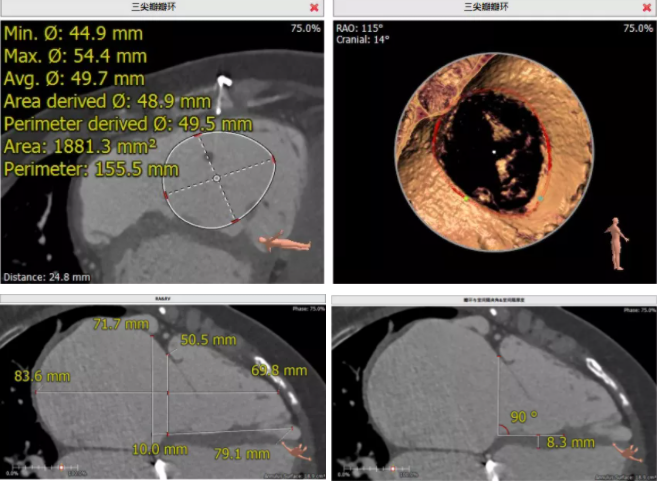

患者為68歲女性,14年前因“反復(fù)感冒、氣促”,檢查發(fā)現(xiàn)心臟瓣膜病,接受了“二尖瓣機(jī)械瓣置換術(shù)”。約5年前出現(xiàn)雙下肢水腫,活動(dòng)后心累氣緊,心臟彩超提示:三尖瓣返流。近年來三尖瓣返流逐漸加重并伴有輕微黃疸、雙下肢水腫,雖長期服用利尿劑治療,但效果欠佳。郭惠明教授團(tuán)隊(duì)結(jié)合病史、超聲及CT評估,考慮患者瓣膜置換術(shù)后,三尖瓣重度返流,再次開胸行體外循環(huán)手術(shù)風(fēng)險(xiǎn)高,經(jīng)團(tuán)隊(duì)整體評估,決定采用最適合患者的LuX-Valve三尖瓣置換系統(tǒng)行微創(chuàng)治療,根據(jù)測量結(jié)果選擇植入JS/TTVI-28-55型號的LuX-Valve瓣膜。

手術(shù)過程